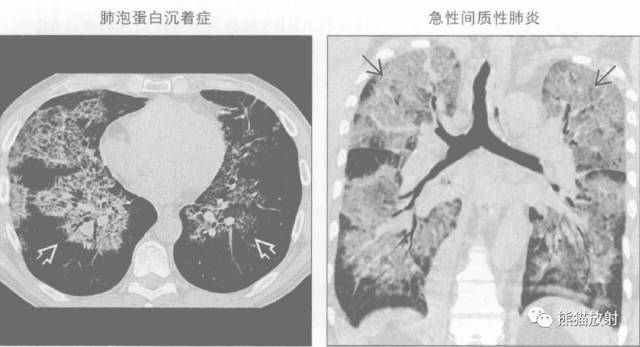

蝙蝠翼征 或 蝶翼征

蝙蝠翼样肺部影是指双侧肺门周围的阴影。

通常在正位胸片上用来描述相关表现,也可指胸部CT上的表现。

蝙蝠翼样肺部影可由以下原因引起:

↓ Pulmonary oedema 肺水肿

↓ 卡氏肺囊虫肺炎